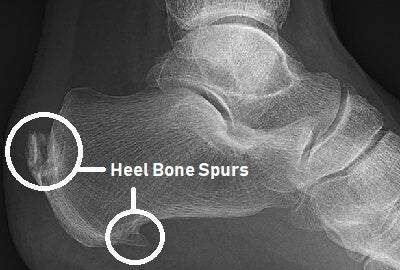

Heel spur or Calcaneal spur and it's symptoms.

Did you have heel pain? Heel spur may be the reason . Read more to know more about heel spur. A calcaneal spur, also known as a heel spur, is...

Calcaneal Spur treatment

Treatment for calcaneal spurs typically involves a combination of self-care measures and medical interventions. Here are some common treatment options: Rest and ice: Resting the affected foot and applying ice...